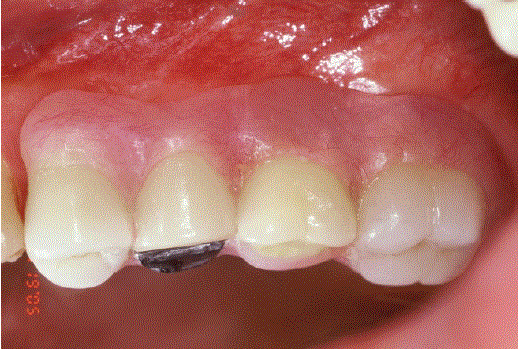

在根分离(#17)后(#17)构建左侧上颌部分CSC-套筒义齿单元(# 14 - #17)的磁性附着内冠(#15)(图1)。图2为部分CSCTD的横视图。带磁性附着体的CSCTD的颊侧和腭侧切面见图3和图4。图4为内冠(#14、#15、#17)的面部视图(图5)、右后视图(图6)和后颊面csc -望远外冠的外观(图7)。

图2:带磁性附着体的csc -望远冠的横切面图(# 14)。